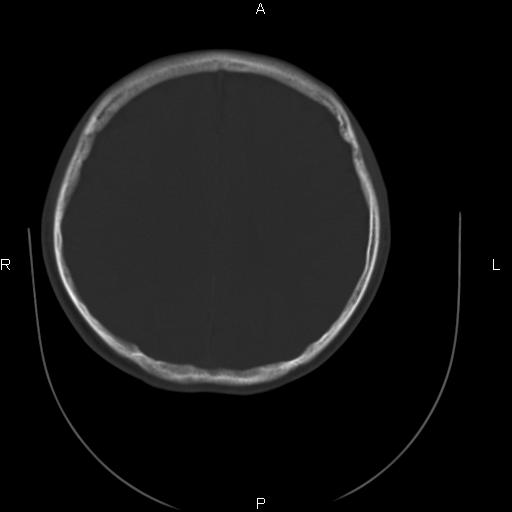

标题: CT27115:大家看一看,这孩子的颅骨表现? [打印本页]

标题: CT27115:大家看一看,这孩子的颅骨表现?

两名中学生打架,脑质内未见异常,未上传。

两例——颅骨结构正常,未见明显骨折征象。

感觉第2个颅缝密度高,额顶部板障有点厚,正常变异?地中海贫血?